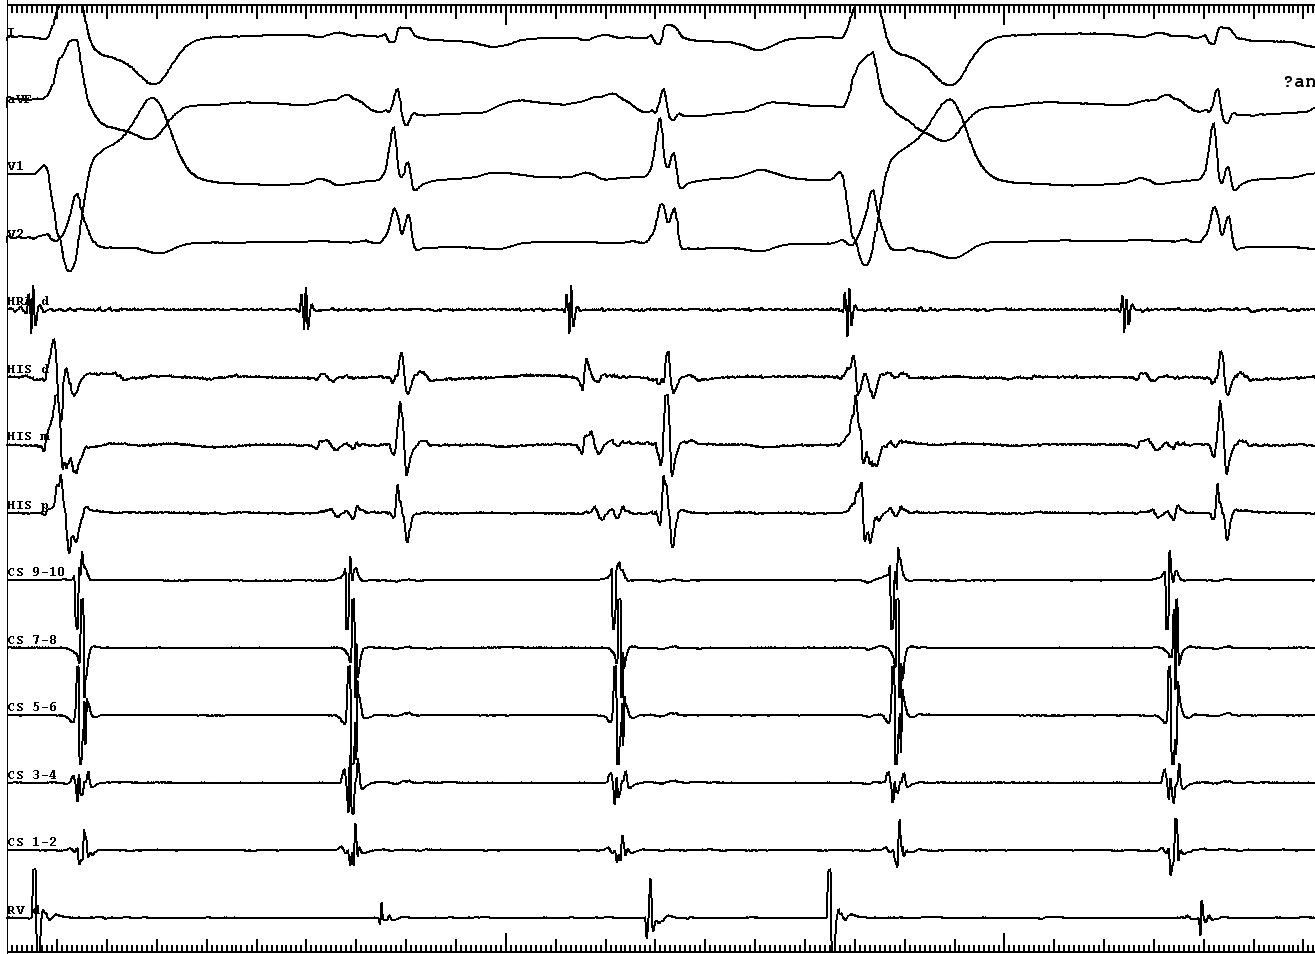

• Short VA during tachycardia - not AVRT

• Narrow QRS similar to sinus - antegrade conduction through another AV node

tachy_4.jpg

• VA conduction with His after A - bystander His activation, ? AP

• VH block with VA conduction - further confirms bystander His

• Internodal tachycardia ? - A before His, tachy continues with VH block

• Therefore, AVNRT involving inputs to anterior node